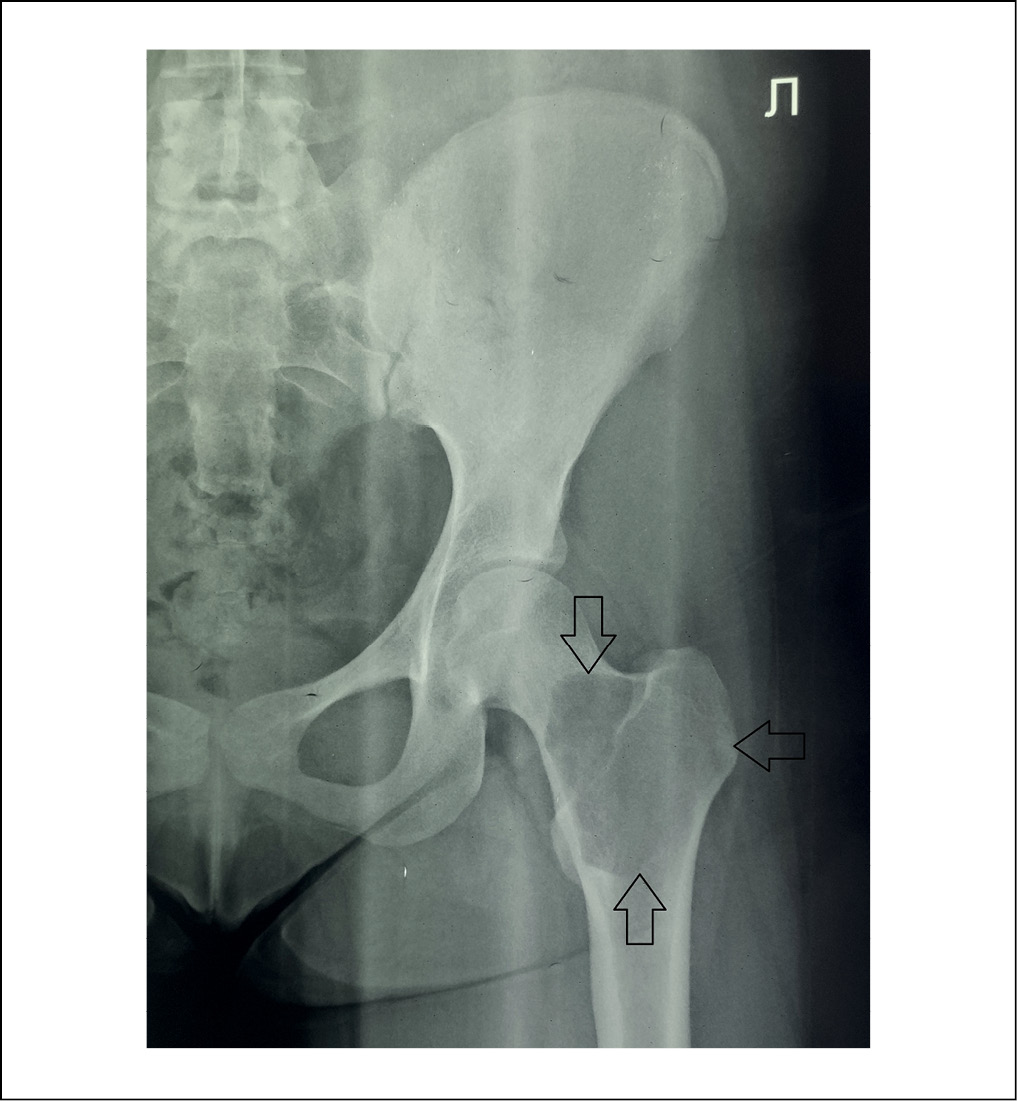

Армирование зоны расположения солитарной костной кисты не выполнялось ввиду анатомической особенности расположения патологического очага – очаг занимал обширную область шейки бедренной кости с распространением на базальную и вертельную зону до уровня малого вертела, а также затрагивал головку бедренной кости, что затрудняло установку винтов. По той же причине не выполнялась и коррекция сформированной варусной деформации проксимального отдела бедренной кости – шеечно-диафизарный угол (ШДУ) составлял 86°. Выполненная интраоперационно контрольная рентгенография левого тазобедренного сустава демонстрировала полное замещение полости костной кисты спонгиозным гомотрансплантатом (рисунок 2). Нижняя конечность была иммобилизирована в кокситной полимерной повязке на срок 8 недель.

Рисунок 2. Интраоперационная рентгенограмма левого тазобедренного сустава пациентки К., 2000 г.р., 2018 г. Отмечаются признаки наличия базального перелома бедренной кости в зоне солитарной костной кисты, смещения отломков с тенденцией к варусной деформации, ШДУ 86°. Полость кисты полностью заполнена гомотрансплантатом. / Figure 2. Intraoperative radiograph of the left hip joint of patient K., born in 2000, 2018. There are signs of a basal fracture of the femur in the area of the solitary bone cyst, displacement of fragments with a tendency to varus deformity, NSA 86°. The cyst cavity is completely filled with homograft.

В послеоперационном периоде проводилась антибактериальная, симптоматическая, обезболивающая терапия. Контрольная рентгенография, выполненная на 8 неделе с момента операции после снятия иммобилизирующей повязки, демонстрировала признаки консолидации перелома со смещением отломков в положении варуса и прогрессирующей реорганизации костного гомотрансплантата (рисунок 3). Пациентка получала полноценное реабилитационное лечение.

Рисунок 3. Контрольная рентгенограмма левого тазобедренного сустава пациентки К., 2000 г.р., через 8 недель с момента получения травмы. Консолидация перелома с варусным положением отломков. Признаки реорганизации гомотрансплантата, формирование регенерата в области костной пластики. / Figure 3. Control radiograph of the left hip joint of patient K., born in 2000, 8 weeks after the injury. Consolidation of the fracture with the varus position of the fragments. Signs of homotransplant reorganization, regenerate formation in the area of bone grafting.